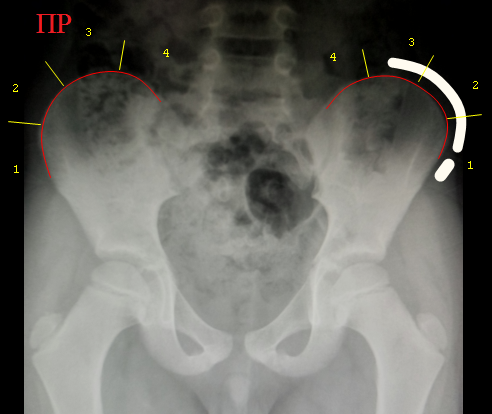

Пример

разметки края крыла подвздошной кости у ребенка 7 лет (ядра окостенения не

определяются, следовательно признак Риссера равен 0). На левой стороне снимка для примера проведена полстая белая линия,

имитирующая ядро окостенения гребня крыла подвздошной кости для признака

Риссера III. Маленький белый овал имитирует ядро окостененения

передней подвздошной ости.